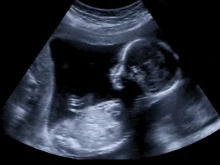

Texas judge rules states can revive challenge to abortion pill

By Kate Quiñones

Trump-appointed Judge Matthew Kacsmaryk ruled Thursday that Idaho, Kansas, and Missouri can pursue legal action to prohibit the FDA from... Read more